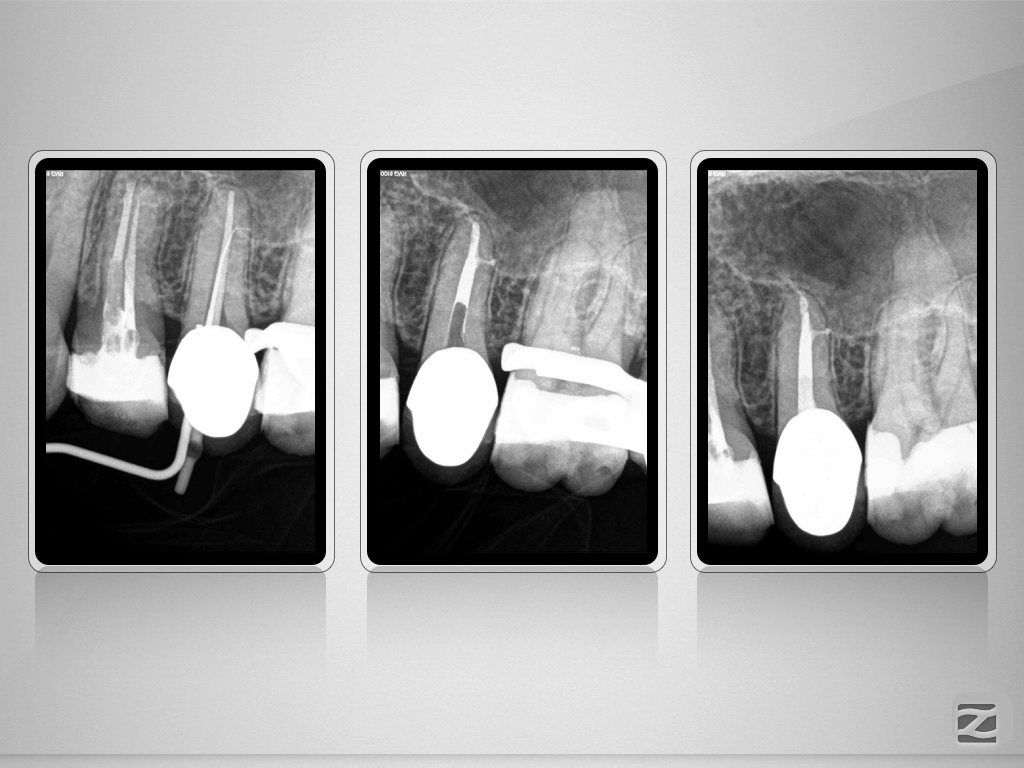

15D.006

Therapieplanung in 3D